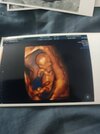

Ja już po. I moje sny były prorocze. Będzie chłopiec. Wszystko jest ok. Kość nosowa i przezierności karkowa w normie a oto pamiątkowe zdjęcia. Tylko datę wczorajsza wpisal.

Załączniki

• 892a589a-1733-44ca-98bf-d460c3572454.jpeg

892a589a-1733-44ca-98bf-d460c3572454.jpeg

35,4 KB · Wyświetleń: 186